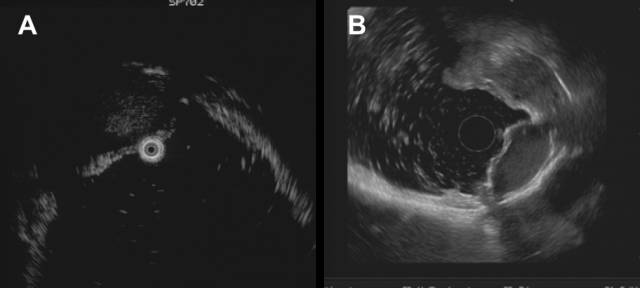

2.副脾外压

副脾是该区域常见的外压,其形成的隆起较小,内镜表现与间质瘤极相似,曾有报道被当成SMT误切,故要提高识别副脾的能力。下面病例副脾外压明确,因为外侧可见正常脾脏,CT等影像学工具诊断副脾时也通常以脾脏为对照,但在无对照时(脾切后),诊断就相对困难。

A:胃底贲门下方隆起;B:胃壁外可见副脾(其外侧可见脾脏结构)

经典EUS教课书上强调用胃壁五层结的完整性来判断外压,但胃底需倒镜探查,EUS扫描平面很难垂直于病灶且信号衰减明显,识别五层结构困难。此时,观察重点应是病灶的内部回声特点,小间质瘤内部为均匀低回声,这和副脾的点状回声完全不同。打个比方,如果让你分辨一只小老虎(间质瘤)和一个家猫(副脾),你可以通过步态和皮毛来判断(相当于观察胃的五层结构),也可以试图掐一下它们,如果发出“瞄”的声音就是家猫(相当于观察病灶内部的回声特点),下面的病例也是通过上述方法诊断为副脾。

该患者也有脾切除病史,胃镜发现胃底隆起,小探头超声见卵圆形病灶,后方膈肌,内部为典型的均匀点状回声,故诊断副脾,从上述两个病例可以看到,如碰到脾切除后的胃底粘膜下隆起,一定要有副脾增生外压的意识。

正常人群也有副脾外压,但是外压较小,同样可通过观察内部回声来判断。

下面副脾形成一个黄豆大小外压。